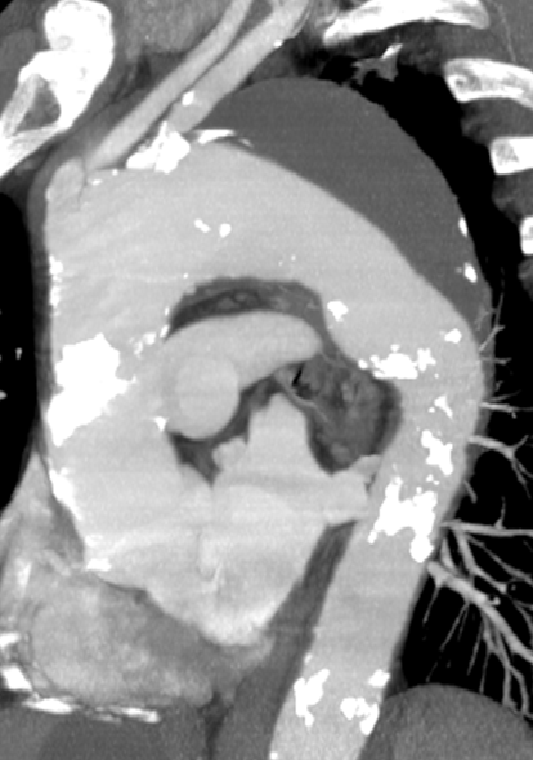

ZIPPERTM支架系统(Zhang Invented Percutaneous Permanent Endovascular Repair, ZIPPERTM Endograft System)是张玮教授团体自主研发的完全经皮经股动脉治疗主动脉弓部病变的新型支架。

目前ZIPPERTM支架系统已应用于临床试验,体现出完全微创、操作简单、疗效确切、安全等优点。[3,4]

[3] Dong, Honglin et al. “First-in-man ZIPPER™ endograft system for the treatment of symptomatic aortic arch intramural haematoma.” European heart journal. Case reports vol. 7,11 ytad574. 17 Nov. 2023, doi:10.1093/ehjcr/ytad574

[4] Fu, Weiguo et al. “Total Percutaneous Transfemoral Endovascular Treatment of Non-A Non-B Aortic Dissection.” JACC. Case reports vol. 30,1 102756. 4 Dec. 2024, doi:10.1016/j.jaccas.2024.102756